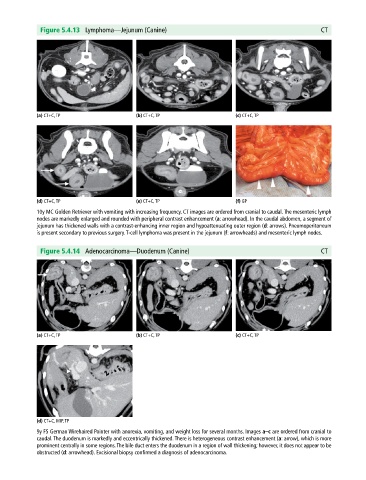

Figure 5.4.13 Lymphoma—Jejunum (Canine) CT

(a) CT+C, TP (b) CT+C, TP (c) CT+C, TP

(d) CT+C, TP (e) CT+C, TP (f) GP

10y MC Golden Retriever with vomiting with increasing frequency. CT images are ordered from cranial to caudal. The mesenteric lymph

nodes are markedly enlarged and rounded with peripheral contrast enhancement (a: arrowhead). In the caudal abdomen, a segment of

jejunum has thickened walls with a contrast‐enhancing inner region and hypoattenuating outer region (d: arrows). Pneumoperitoneum

is present secondary to previous surgery. T‐cell lymphoma was present in the jejunum (f: arrowheads) and mesenteric lymph nodes.

Figure 5.4.14 Adenocarcinoma—Duodenum (Canine) CT

(d) CT+C, MIP, TP

9y FS German Wirehaired Pointer with anorexia, vomiting, and weight loss for several months. Images a–c are ordered from cranial to

caudal. The duodenum is markedly and eccentrically thickened. There is heterogeneous contrast enhancement (a: arrow), which is more

prominent centrally in some regions. The bile duct enters the duodenum in a region of wall thickening; however, it does not appear to be

obstructed (d: arrowhead). Excisional biopsy confirmed a diagnosis of adenocarcinoma.